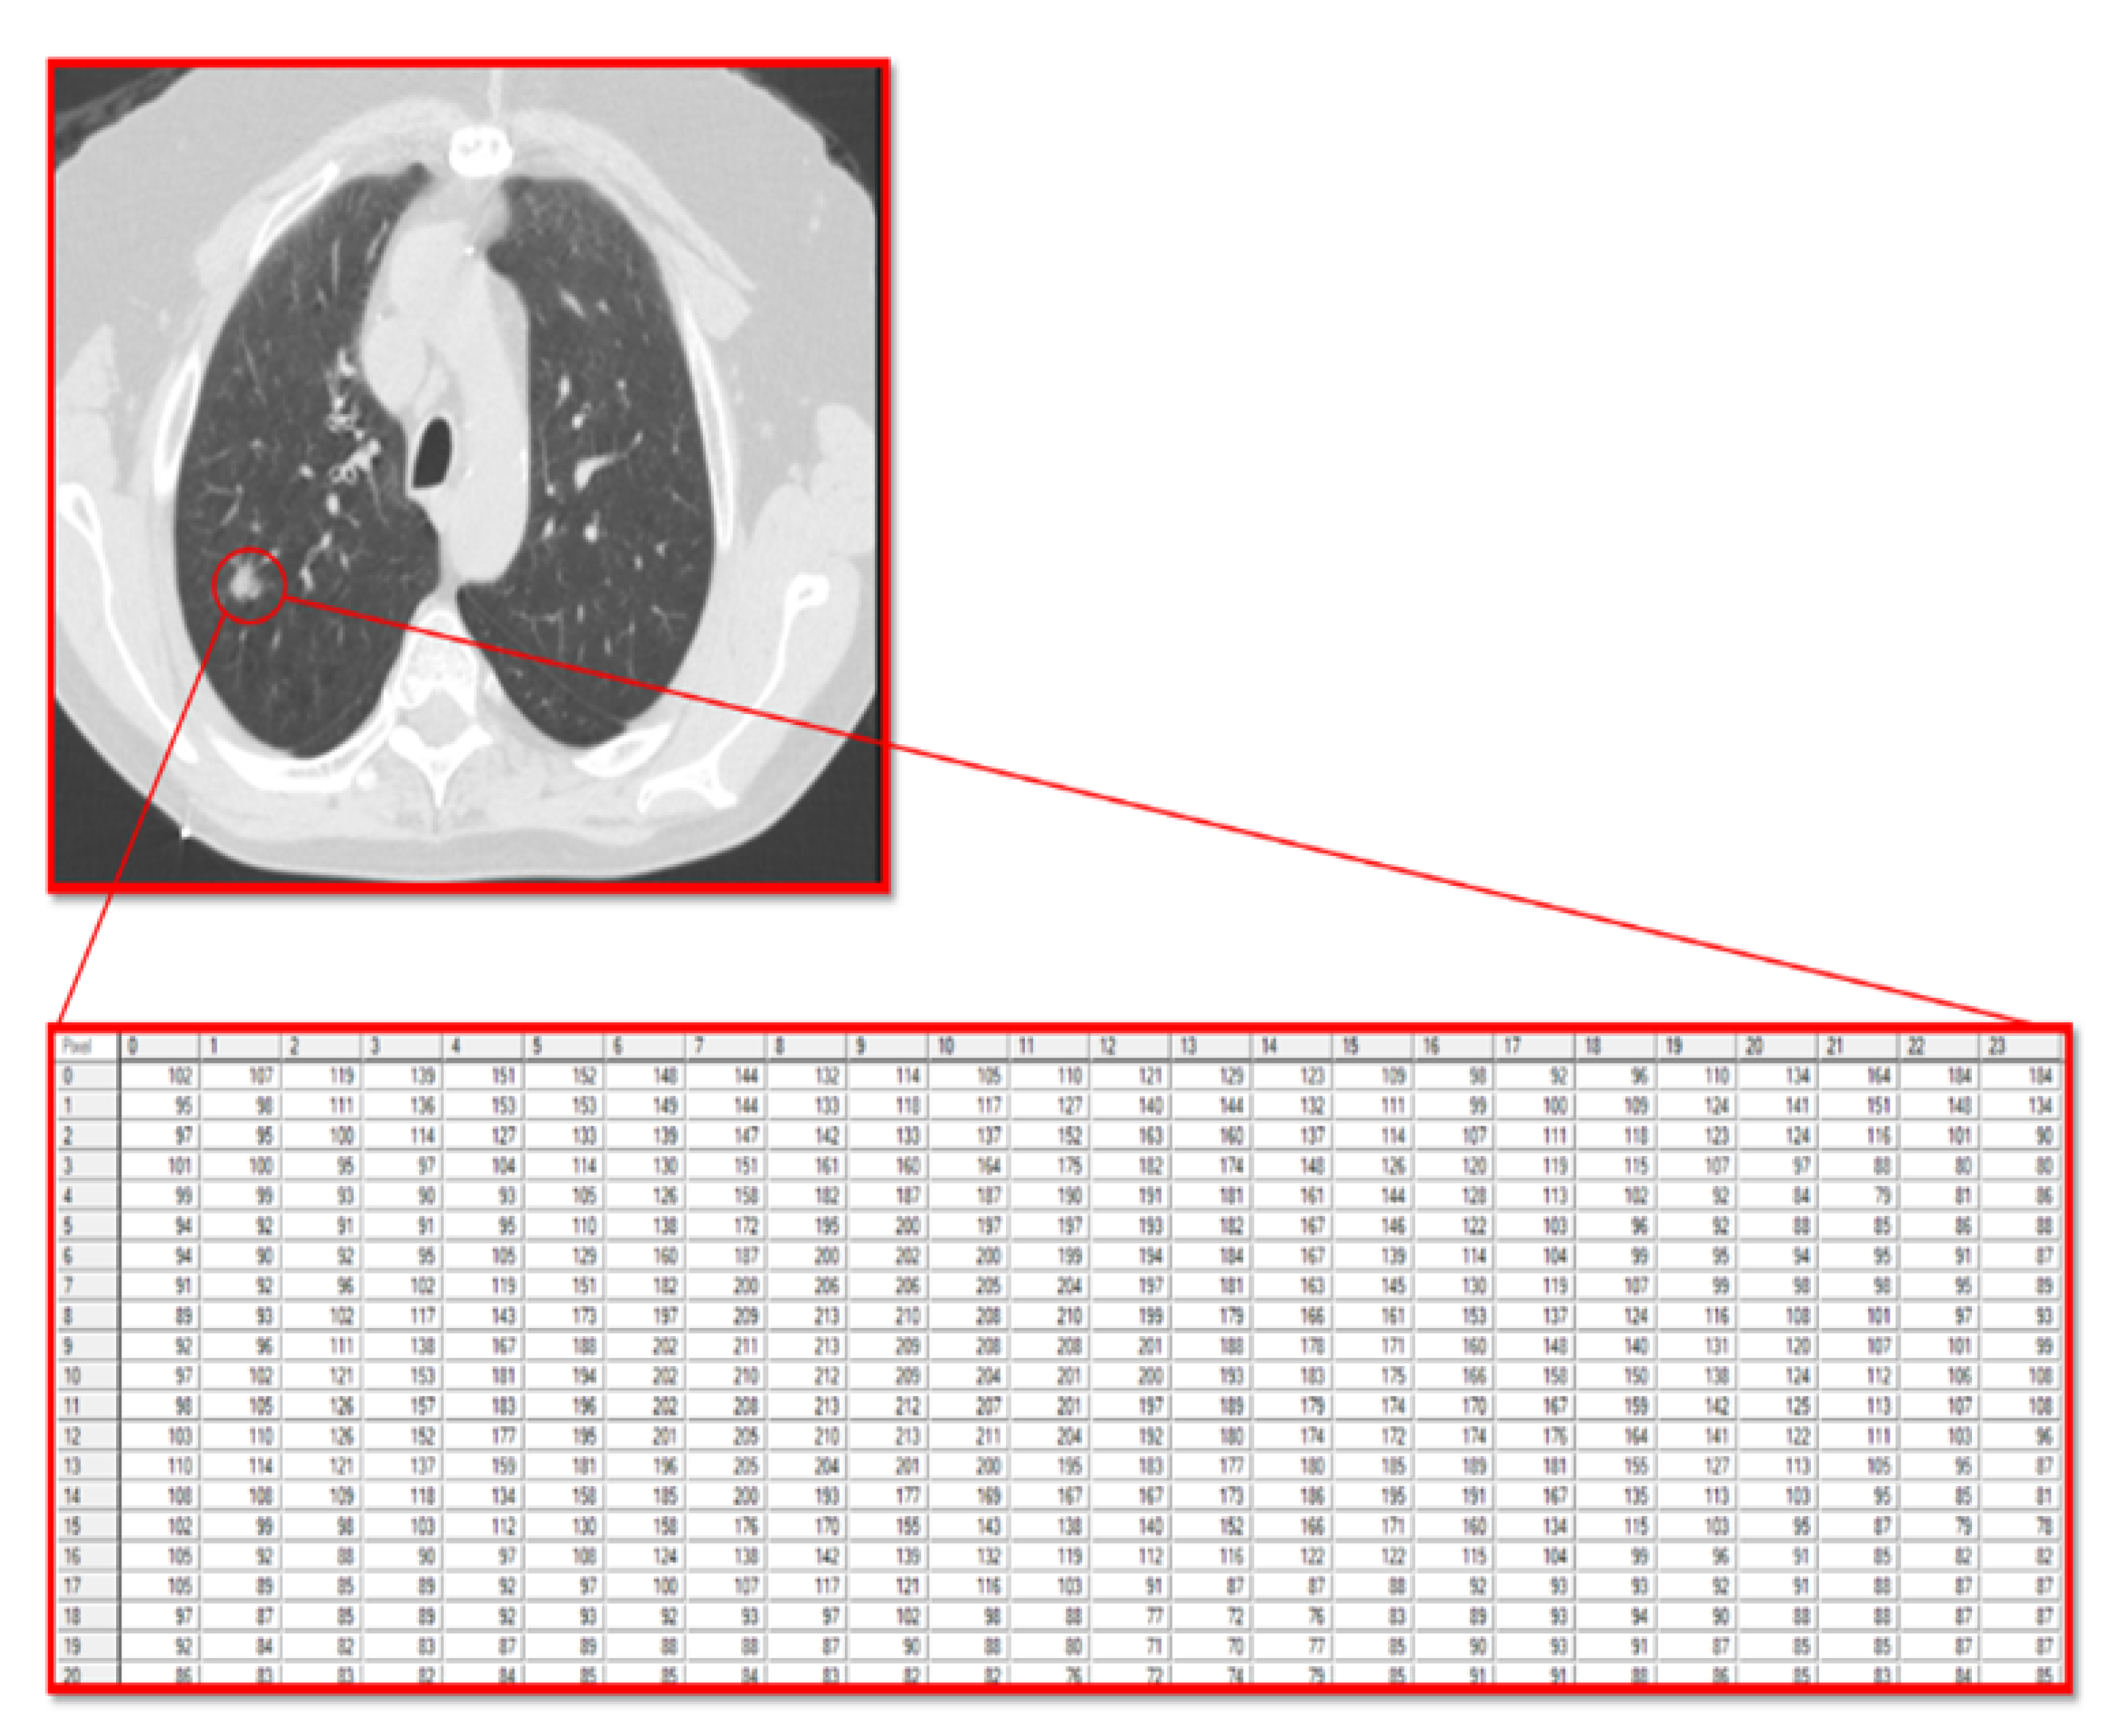

2.4. Work Procedure

The current study utilized the fact that a computer reads a radiographic image as a matrix of pixels with different grayscale values. In this matrix, the numbers are integers that range from 0 (black) to 255 (white), allowing for the analysis of the texture of the pixels that make up the tumor and the stroma accompanying the tumor.

For texture analysis, a digital technology called MaZda (version 4.6) was used [27]. To calculate the texture variables of the GGO lesions in the radiographic image, an annotation of the tumor region was performed. Subsequently, the software calculated the texture variables (Figure 1).

Figure 1. Lung CT scan with ground-glass opacity (GGO). The GGO lesion is marked with a circle, and the pixel matrix shows the tumor texture. A zoomed-in view of the grayscale pixel intensities used for texture analysis. In this matrix, grayscale values are integers that range from 0 (black) to 255 (white), allowing for the analysis of the texture of the pixels that make up the tumor and the stroma accompanying the tumor.

Jcm 14 08082 g001